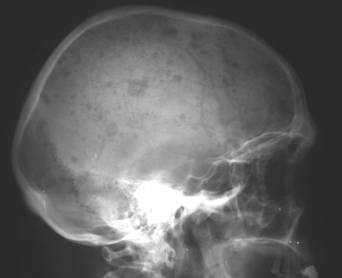

Radiografic se pot constata:

Fisuri craniene

Fracturi nedenivelate (liniare, cominutive, disjunctii suturare, f 656b14g racturi-disjunctie);

Fracturi denivelate (evulzive, cu extruzie si depresive, cu infundare);

Fracturi complexe (cranio-otice, cranio-sinusale, etc).

Fig. 98 – Fractura de bolta caraniana fronto-parietala stanga si parieto-temporo-occipitala dreapta